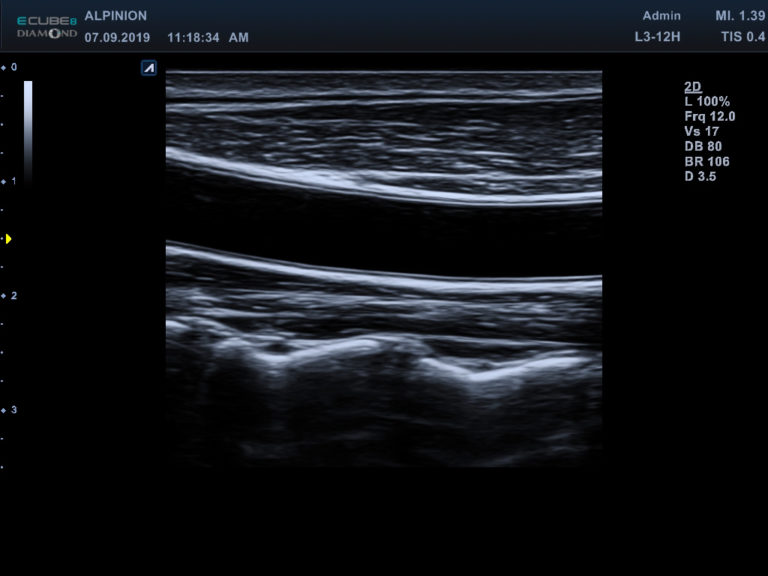

Ultrasonograf Alpinion E-CUBE 8 to jeden z najczęściej wybieranych systemów do badań naczyniowych.

Potwierdziło to już bardzo wielu lekarzy, potwierdzają to także obrazy kliniczne uzyskane przez naszych inżynierów.

Wybrane obrazy kliniczne